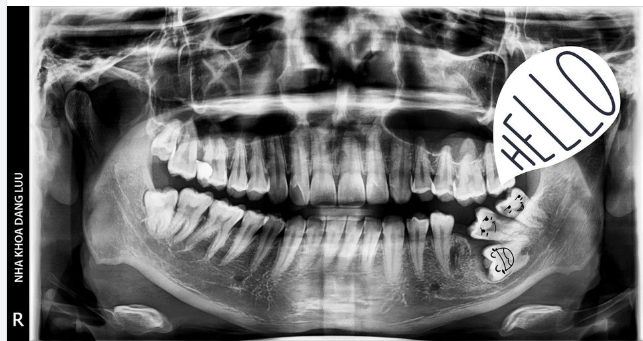

Nhổ răng khi niềng có bị hóp má & ảnh hưởng đến tổng thể khuôn mặt?

Do đó, má chỉ bị hóp khi ăn nhai kém, các khối cơ không còn nơi nâng đỡ hay làm đầy, theo cơ chế tự nhiên sẽ bị chùng xuống gây hiện tượng hóp má. Việc nhổ răng để niềng là tạo khoảng trống để các răng dịch chuyển và vùng khoảng mất răng này sẽ nhanh chóng được đóng lại, nên không phải lo lắng niềng răng bị hóp má.